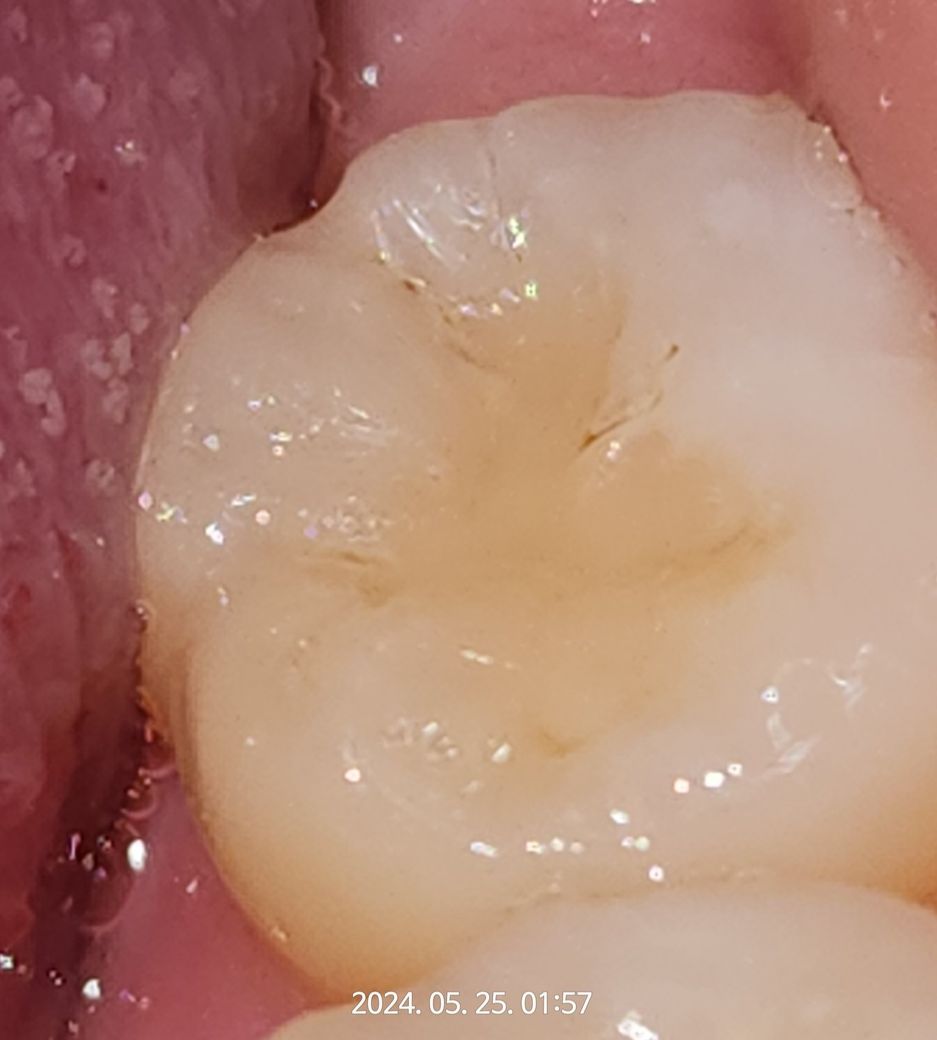

어금니 레진 떼운곳에 2차 충치가 생긴건가요?

어금니에 레진 떼운지는 2달이 조금 넘었는데요

거뭇거뭇 한게 조금 보이는데요 이게 2차 충치인가요?

아니면 그냥 착색,변색된걸까요??

사진으로 봤을 경우에는 충치라기보다 착색이 된 것으로 보입니다 착색은 치아 홈이나 충전재 경계 부분에 생기는 경우가 있는데 크게 문제를 발생시키지 않기 때문에 너무 걱정하지 않으셔도 됩니다 자세한 확인을 위해서 치과에서 진료를 받아 보는 것을 권유 드립니다

• 현재 사진만으로는 정확한 판단이 어렵습니다. 2차 충치일 가능성도 있고, 착색일 수도 있습니다. 치과 방문 후 임상 검사 기구로 해당 부분을 검사해보아야 합니다. 사진만으로는 정확한 답변이 어렵습니다.

• 사진만 봐서는 충치인지 착색인지 구분이 되지 않습니다. 살짝 다듬어보고 없어지면 착색이고 아니면 충치라고 판단합니다. 치료하신지 얼마 되지 않았으니 치료받으신 치과에 가셔서 문의 해보시면 설명과 함께 그에 맞는 조치를 해주실 것 같습니다.

• 어금니 레진으로 떼우고 주변부분에 추가적인 충치가 발생한 것으로 보입니다. 하지만 충치가 진행이 되지 않는 정지형인 경우에는 양치를 꼼꼼히 하면서 상태를 지켜보길 권합니다.